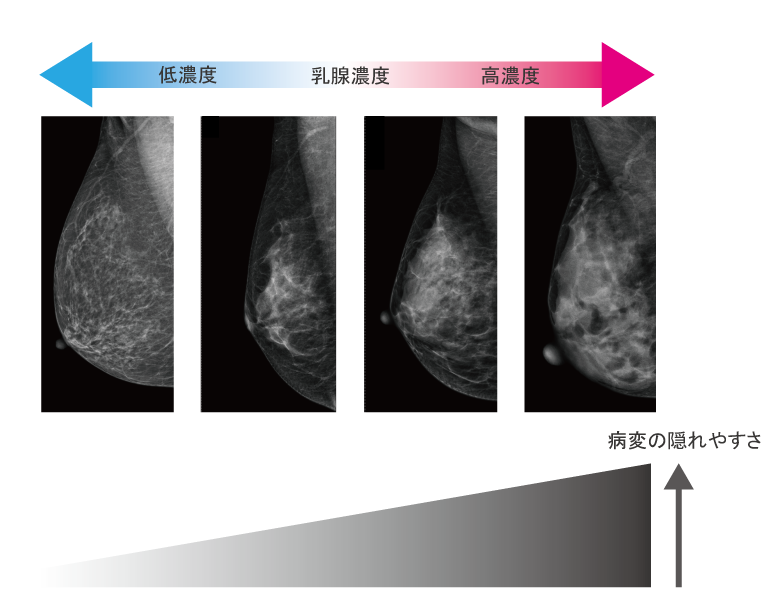

乳腺濃度について

- マンモグラフィの画像では乳腺が白く写ります。一般的に乳腺は年齢とともに減少していきます。

- 乳腺濃度が高く、画像上白い部分が多い乳腺は「高濃度乳房」と呼ばれます。

- 日本人は「高濃度乳房」が多いとされています。

- がんも乳腺同様、画像上白く写り、「高濃度乳房」では病変が発見しづらくなります。